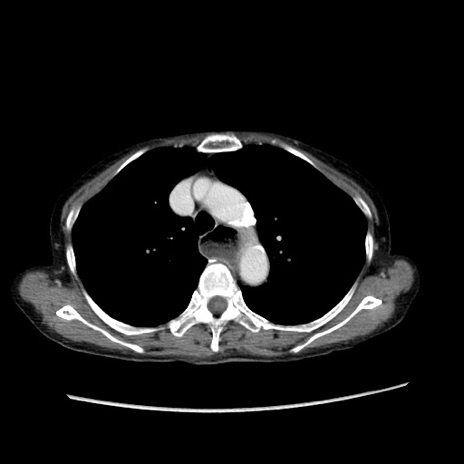

症例25(横断像)

【症例】80歳代女性

【主訴】胸のつかえ感

【現病歴】約9時間前に食後から胸のつかえた感じあり、嘔吐あり、来院。

【既往歴】胃癌(全摘)、胆摘、虫垂炎

【身体所見】心窩部に圧痛あり、反跳痛なし。

【データ】WBC 5700、CRP 0.05